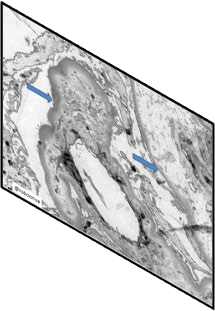

With the rapid development of self-supervised learning (e.g., contrastive learning), the importance of having large-scale images (even without annotations) for training a more generalizable AI model has been widely recognized in medical image analysis. However, collecting large-scale task-specific unannotated data at scale can be challenging for individual labs. Existing online resources, such as digital books, publications, and search engines, provide a new resource for obtaining large-scale images. However, published images in healthcare (e.g., radiology and pathology) consist of a considerable amount of compound figures with subplots. In order to extract and separate compound figures into usable individual images for downstream learning, we propose a simple compound figure separation (SimCFS) framework without using the traditionally required detection bounding box annotations, with a new loss function and a hard case simulation. Our technical contribution is four-fold: (1) we introduce a simulation-based training framework that minimizes the need for resource extensive bounding box annotations; (2) we propose a new side loss that is optimized for compound figure separation; (3) we propose an intra-class image augmentation method to simulate hard cases; and (4) to the best of our knowledge, this is the first study that evaluates the efficacy of leveraging self-supervised learning with compound image separation. From the results, the proposed SimCFS achieved state-of-the-art performance on the ImageCLEF 2016 Compound Figure Separation Database. The pretrained self-supervised learning model using large-scale mined figures improved the accuracy of downstream image classification tasks with a contrastive learning algorithm. The source code of SimCFS is made publicly available at https://github.com/hrlblab/ImageSeperation.